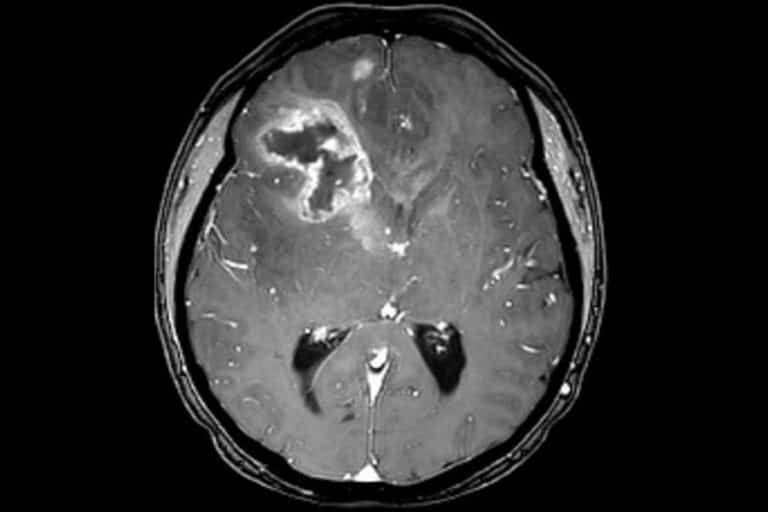

Unter sekundäre Kopfschmerzen fallen eine Vielzahl von Kopfschmerz-Syndromen welche eine andere Erkrankung als Ursache haben. Hierzu zählen zum Beispiel Hirnblutungen (z.B. bei Gerhirnaneurysmen) und Tumore. Diese sind jedoch sehr selten.